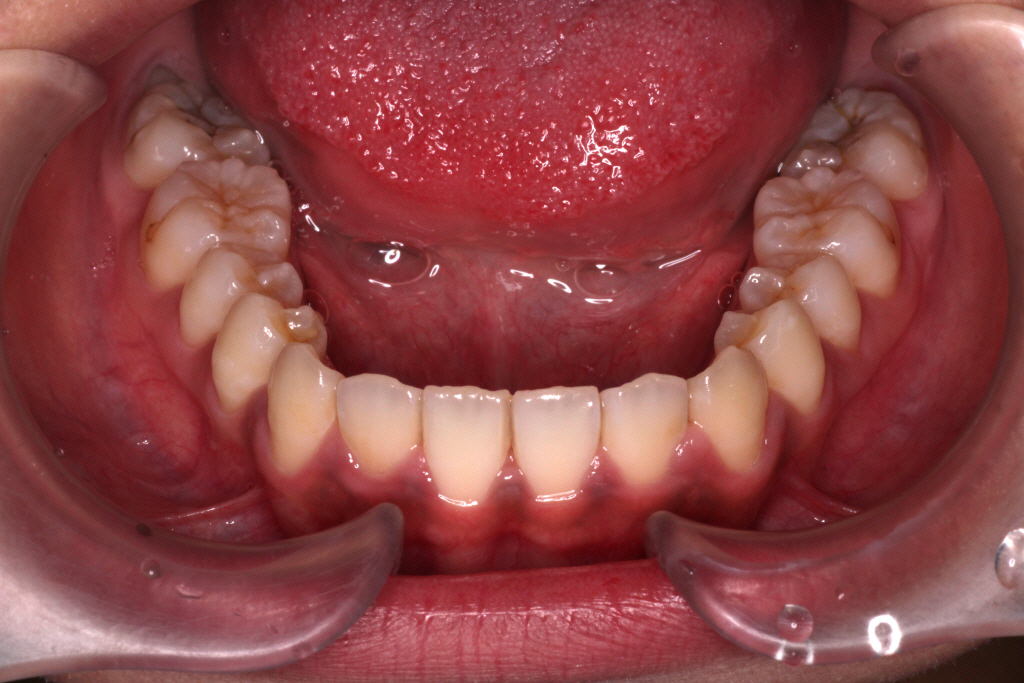

初診時のお口の中の状態です。

上の前から2番目の歯が下の歯列より内側にあり叢生です。

側方の上下の咬合関係が理想の上1本に対して下2本の理想的な噛み合わせではない。

歯列の幅がせまい。